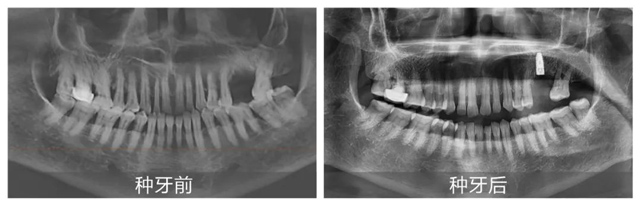

“在日常诊疗中,我们会依据患者的口腔情况一对一量身定制种植方案。而新桥口腔特别开设的数字化特检科,可通过数字化CBCT影像、3D口扫等完成术前一站式检查,规避后续治疗中可能存在的风险与误差。”李丹主任还表示:“定期开展的种植牙手术直播,通过实时转播医生的操作过程与顾客亲身讲述就诊体验,可以让市民直观感受到数字化种植的诸多优点!”

在李丹主任细致讲解的同时,手术室已准备就绪,上午10:32分,手术正式开始。从术前消毒到定量麻醉,从定点备洞到精准植入,再到最后的严密缝合,黄杰医生始终有条不紊地依序进行。手术全程都由李丹主任与吴海燕主管同步配合讲解,现场观众纷纷对黄杰医生的精湛技术拍手称赞。